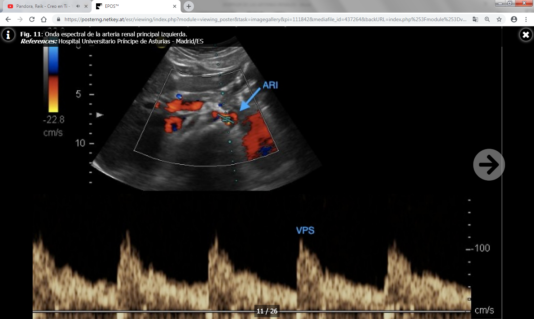

Los parámetros directos son más fiables y reproducibles que los indirectos, y son los siguientes:

- Velocidad picosistólica (VPS) : Normal por debajo de 180-200 cm/s.

- Índice reno-aórtico (cociente entre la VPS de la arteria renal y la aorta): Normal por debajo de 3.5-3.6.